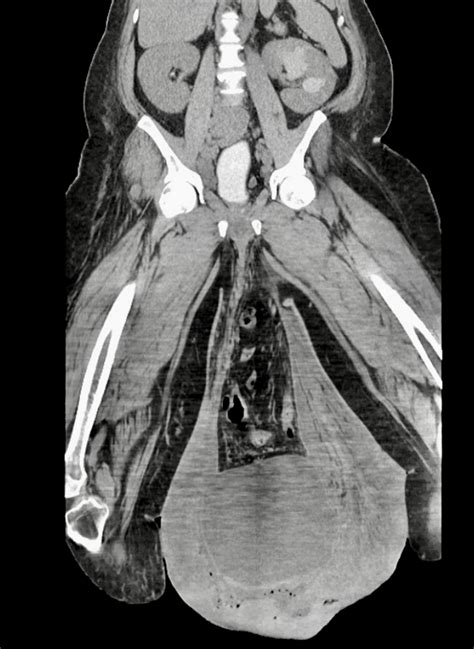

Elephantitis Of The Testicals

Elephantitis of the testicals, also known as elephantiasis of the scrotum, is a rare and severe condition characterized by the enlargement of the scrotum due to lymphatic obstruction. This condition is typically caused by filariasis, a parasitic infection transmitted by mosquitoes. Understanding the causes, symptoms, diagnosis, and treatment options for elephantitis of the testicals is crucial for effective management and prevention.

• Scrotal Swelling: The most noticeable symptom is the enlargement of the scrotum, which can become massive in severe cases.

• Skin Changes: The skin of the scrotum may become thickened, hardened, and discolored.

• Mobility Issues: The enlarged scrotum can interfere with mobility and daily activities.